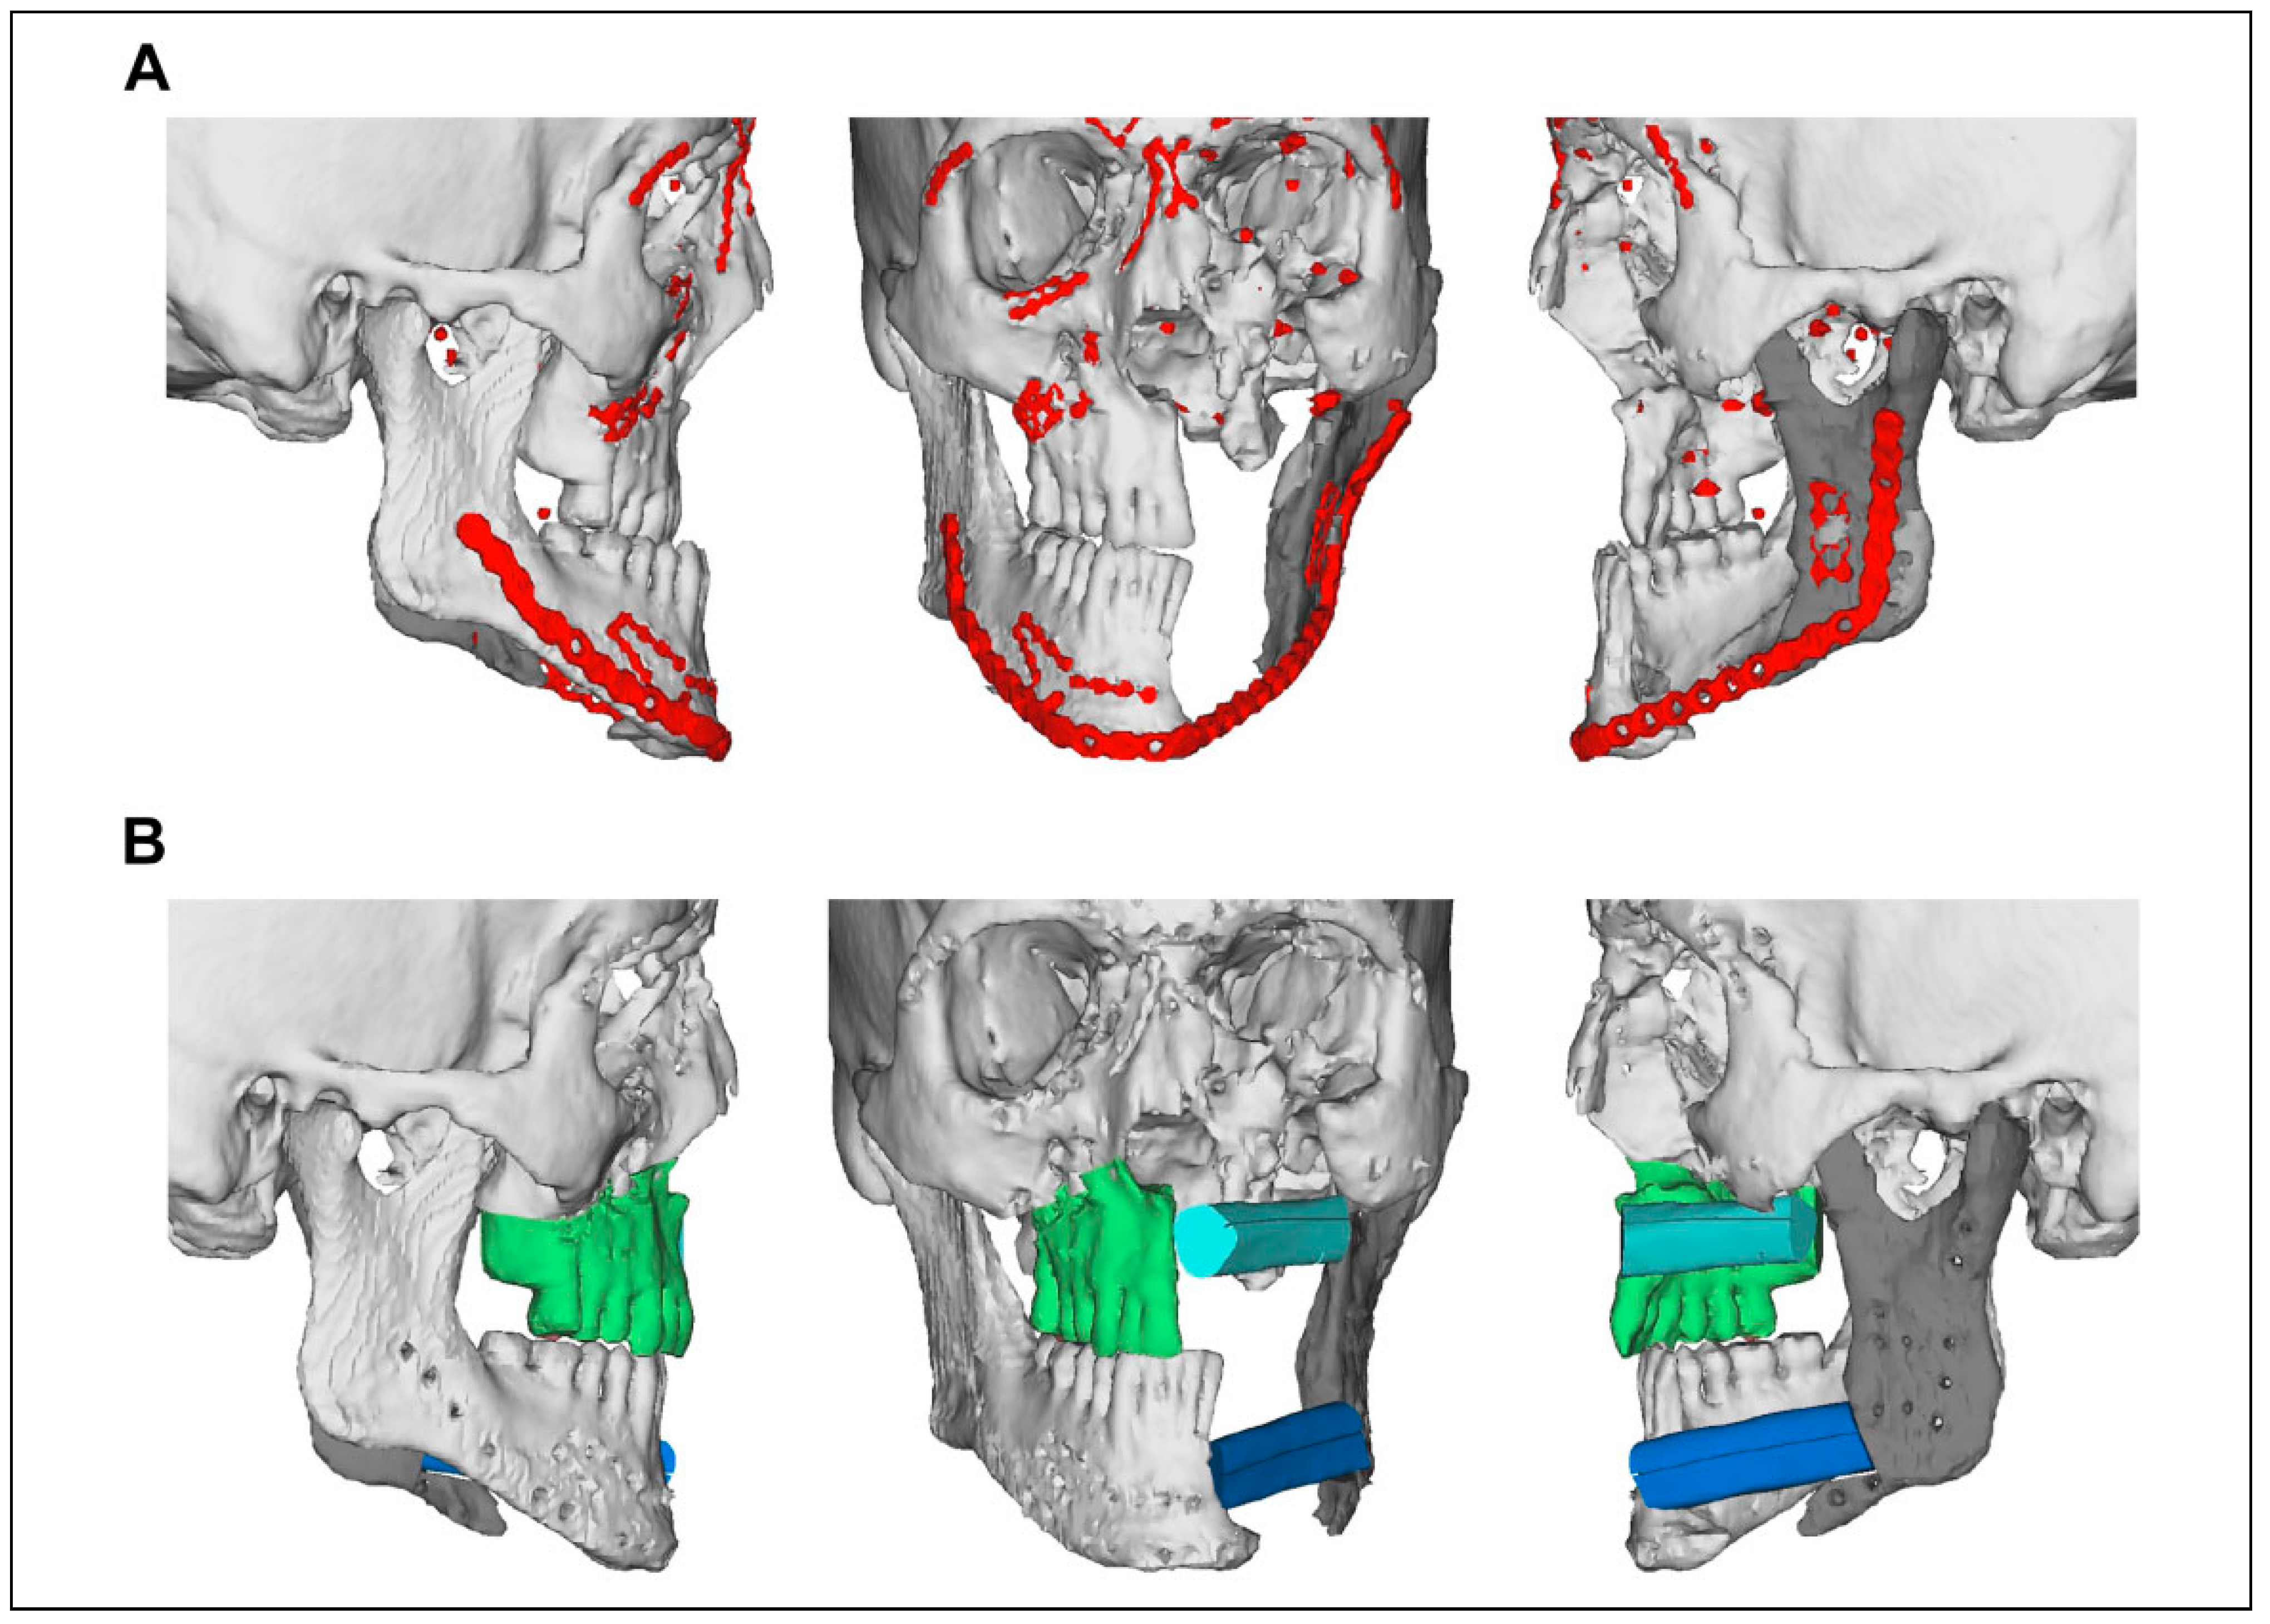

Case Series

Case Presentations